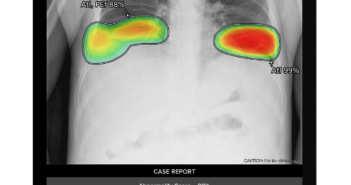

의료 인공지능(AI) 기업 루닛이 삼성전자와 AI 솔루션 2개 제품에 대한 공급 계약을 체결했다. 계약금액은 3년간 186만 달러(한화 약 25억원)로다. 이번 계약에 따라 루닛은 흉부 엑스레이 AI 영상분석 솔루션 '루닛 인사이트 CXR'과 응급질환 AI 자동분류 솔루션 '루닛 인사이트 CXR 트리아지'를 삼성전자에 공급한다. 삼성전자는 프리미엄 이동형 및 고정형 엑스레이 촬영장비에 루닛 AI 솔루션을 설치하여 해외 주요 국가에 판매할 예정이다. 루닛 인사이트 CXR은 흉부 엑스레이 영상에서 폐결절, 섬유화, 석회화 등 10가지 흉부 질환을 검출해 의료진의 진단을 보조하는 AI 솔루션이다. 루닛 인사이트 CXR 트리아지는 기흉, 흉수 등 응급 질환의 정상 및 비정상 소견을 자동분류하는 AI 솔루션으로, 지난 2021년 11월 미국 식품의약국(FDA)의 허가를 획득했다. 양사는 AI 솔루션을 탑재한 엑스레이 촬영장비를 미국, 캐나다 등 북미지역과 유럽시장에 집중 판매하는 한편, 중동, 남미, 동남아 시장까지 판매망을 넓혀나갈 계획이다. 특히 루닛 인사이트 CXR 트리아지가 응급을 요하는 영상정보를 빠르고 정확하게 분류하는 데 강점이 있는 만큼, 병원 중환자실 및 응급실을 대상으로 영업력을 집중할 예정이다. 서범석 루닛 대표는 "루닛은 GE헬스케어, 필립스, 후지필름 등 글로벌 의료기기 리딩 기업들과 파트너십을 맺고 시장 확대에 노력한 결과, 현재 전 세계 3천 곳 이상의 의료기관에 AI 솔루션을 공급하고 있다"며 "프리미엄 엑스레이 촬영장비 개발을 통해 경쟁력을 갖춘 삼성전자와의 이번 파트너십은 양사의 글로벌 시장점유율을 한차원 더 높이는 특별한 계기가 될 것"이라고 말했다. 관련 기사 더보기 https://www.venturesquare.net/906701